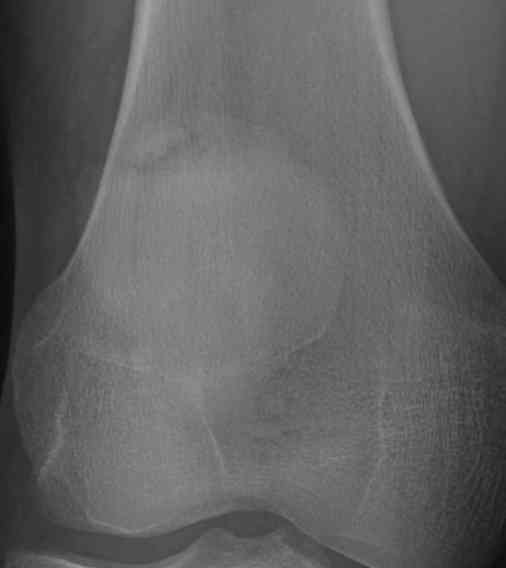

Classically superolateral

Classification Saupe

I Inferior Pole 5%

II Lateral 20%

III Superolateral 75%

Xray